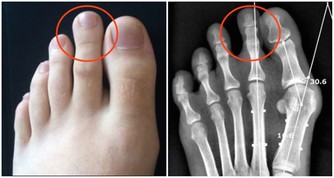

美國一名42歲的男子去非洲奈及利亞旅遊,當時他發現自己腳上的血管變得很清楚。

原本他以為只是類似靜脈曲張所以不在意,但一個月後,他發現這個血管竟然會在他腳步上下移動...

他發現這個痕跡越來越淡,但是位置卻跟以前差很多。

保險起見,他決定找了另一位醫生協助,才發現他腳上的紅色痕跡根本不是血管,是巨大的蠕蟲!